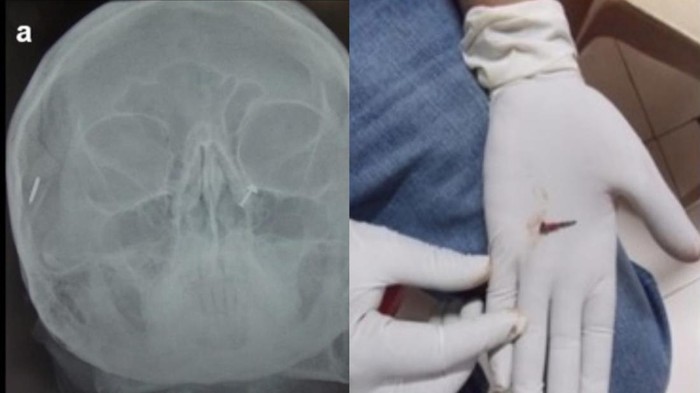

Penampakan benda asing yang ditemukan dalam tubuh.

Perempuan 50 tahun pergi ke rumah sakit dengan keluhan nyeri leher dan kepala lebih dari satu tahun. Setelah dilakukan pemeriksaan mendalam, dokter menemukan sebuah benda asing di kepalanya. Terungkap, pasien pernah mengalami trauma 10 tahun lalu dan tidak mengetahui ada paku tertinggal dalam kepalanya. (Foto: F1000 Research)